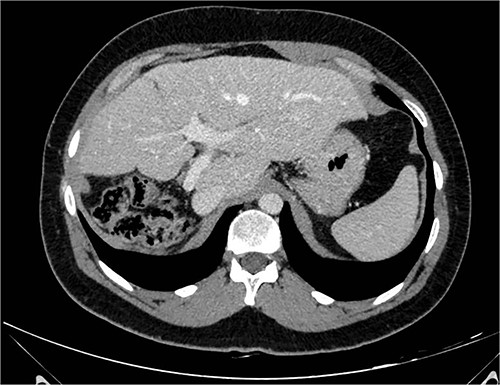

A 26-year-old, previously healthy man was admitted in March 2019 to the Surgical Department of our Hospital with abdominal distension and discomfort in the last 6 months. On physical examination, a palpable large mass was documented in the right hypochondrium extending below the umbilicus with tenderness in the upper abdomen without evidence of ascites. His medical history was little significant, just fraternal twin and hypothyroidism. Laboratory tests were carried out but tumour markers, hepatitis virus markers, and liver enzymes were normal and not diagnostic. Contrast enhanced CT-scan highlighted a giant, hypodense, heterogeneous, solid lesion without cystic component in the right lobe of the liver (Fig. 1). The tumour compressed neighbouring parenchyma and displaced abdominal organs and the retro-hepatic vena cava was also compressed with the middle hepatic vein slightly occluded by thrombotic material. Percutaneous needle biopsies were performed in different areas of the mass. All samples showed mesenchymal tissue with low proliferative index MIB1, and the pathologist suggested diagnosis of MHL. Following a thorough review of the literature, in view of the possibility of malignant degeneration and the high rate of local recurrence, radical liver surgery was proposed. Liver volumetry was measured, and the future liver remnant appeared sufficient to avoid post-operative liver failure. For this reason, liver transplantation was ruled out in favour of right hemi-hepatectomy without segment 1, according to Brisbane classification. In April 2019, the patient was admitted in operatory room after resolution of the middle hepatic vein thrombus with anticoagulant therapy. Right hepatectomy was carried out in 330 min.

The post-operative course was uneventful, and the patient was discharged on 14th post-operative day. Pathologist’s report described a giant solid tumour without cystic component with maximum diameter of 35 cm, 8 kg weighted (Fig. 3) and clear surgical margins. Microscopic study showed a well circumscribed tumour, surrounded by an irregular margin of compressed hepatic parenchyma. Hypo-cellulated loose myxoid stroma was the almost exclusive component in the centre of the tumour, rich of blood and lymphatic vessels but small bile ducts and hepatocyte islands were nearly absent (Fig. 4). The mesenchymal component of the tumour was reactive to desmin and smooth muscle actin. Low proliferation index was confirmed (MIB1).